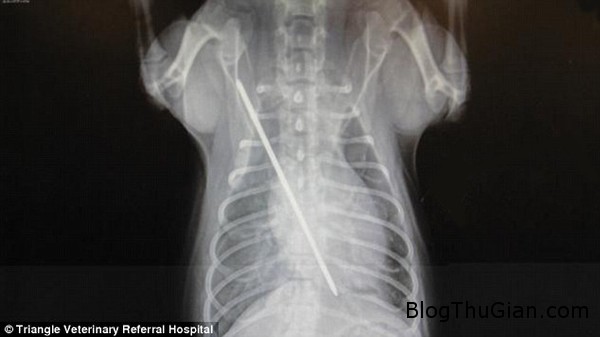

Kết quả chụp X-quang cho thấy, chiếc kim đã xuyên qua ngực và chạm tới tim của Tutti. Điều đáng mừng là Tutti không hoảng sợ mà trái lại có thái độ rất trầm tĩnh. Vì vậy, bác sĩ thú y có thể rút chiếc kim ra một cách dễ dàng sau khi đã tiêm thuốc mê cho nó.